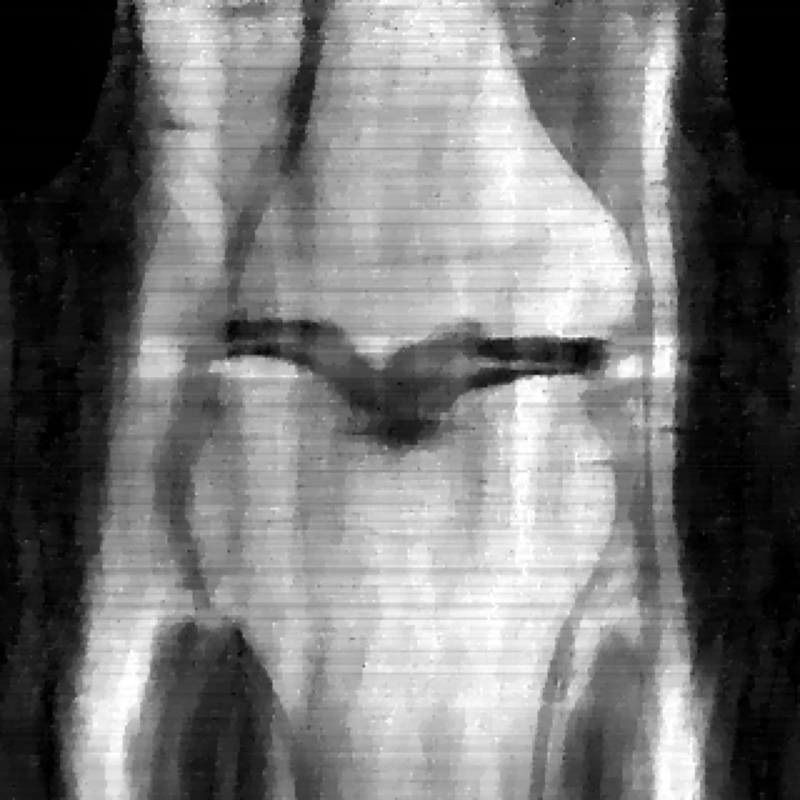

MRI reconstruction is performed with a undersampling of k-space in the phase encoding direction for both and . The sampling maps are shown in Fig 4.

![]() |

| (a) Original k-space sampling pattern () | (b) Resampled k-space sampling pattern () |

In the case of MRI, we use two choices of , depending on whether we assume is fully known or not. In the case is fully known, we utilize another undersampled k-space mask, but with resampled high-frequency lines. We display the original and new k-space sampling masks in Figure 4. To illustrate the utility of our approach under miscalibration of the forward model in an MRI reconstruction setting, we also consider a unknown random perturbation of the original k-space lines, which we attempt to learn during reconstruction. The vertical k-space lines are still fully sampled, as are the center 4 of frequencies, but all high frequency lines are perturbed uniformly at random with a continuous value from -2 to 2. We wish to emphasize that this experiment is not meant to reflect clinical practice, since such miscalibration of k-space sampling locations is not typically encountered in anatomical imaging with Cartesian k-space sampling trajectories. However, we include this experiment simply to illustrate that our approach could be extended to unknown parametric changes in the forward model in an MR reconstruction setting.